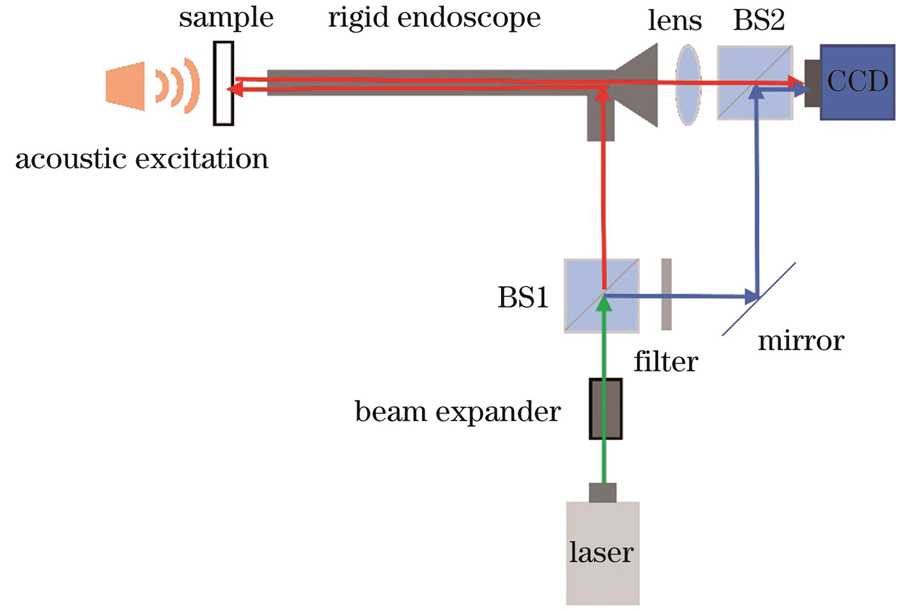

图 2. 数字全息内窥干涉光路示意图

Fig. 2. Schematic of digital holographic endoscopy interference light path

采用马赫-曾德尔数字全息内窥干涉光路实现耳膜离面形变信息的全息图记录。

根据